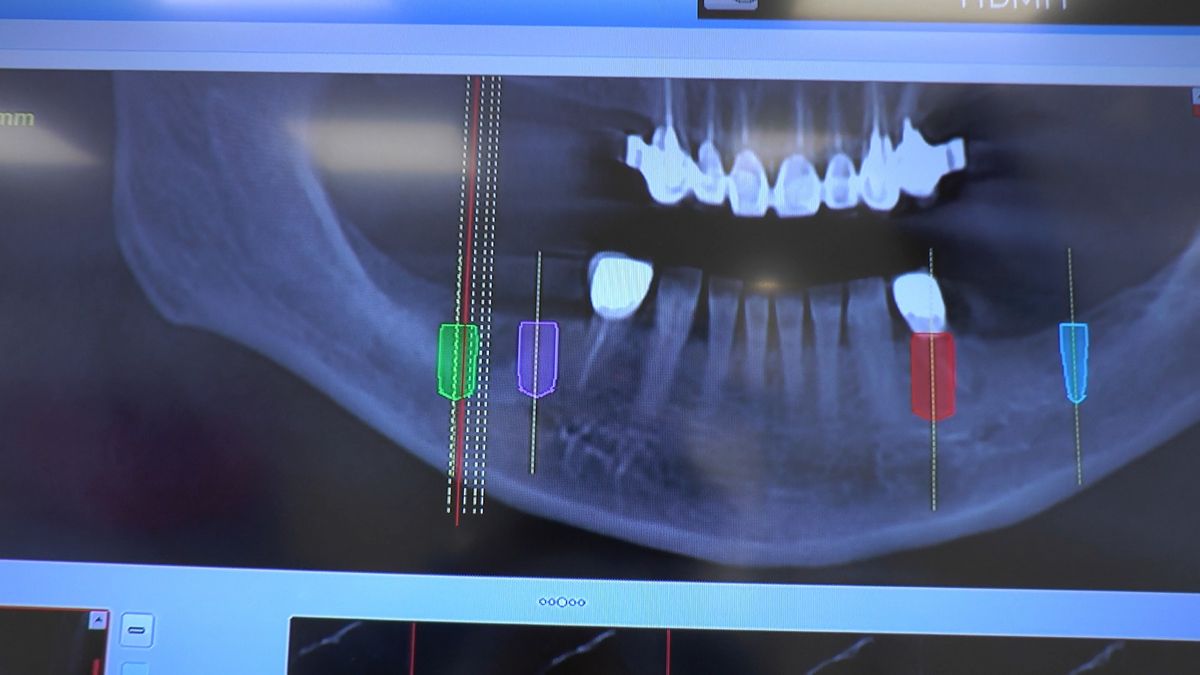

W ostatni weekend czerwca 2018 roku kursanci II Sezonu Preludium Implantologii odbyli piątą, finałową sesję, która w całości podporządkowana była praktyce. W ciągu dwóch dni zabiegowych Lekarze uczestniczący w szkoleniu przeprowadzili szereg zabiegów pod kierunkiem dr n.med. Violetty Szycik. Wszczepili 17 implantów oraz przeprowadzili ekstrakcje i zabiegi regeneracyjne kości. Zabiegi były wykonywane także w sedacji dożylnej z udziałem specjalisty anestezjologii i intensywnej terapii dr Jolanty Grzybowskiej. Preludium implantologii to nowy program edukacyjny dla adeptów implantologii stomatologicznej, którego celem jest wprowadzenie do implantologii poprzez pozyskanie wiedzy w szerokim zakresie i uwzględnieniem szczegółów mających decydujące znaczenie dla powodzenia leczenia implantologicznego. Ale tak jak wszystkie szkolenia w Instytucie Vivadental, w tym wiodące Practiculum Implantologii, zorientowane jest na praktyce i samodzielnym wykonywaniu zabiegów pod kierunkiem Mentora. To najlepsza edukacja w medycynie zabiegowej, a zarazem najlepszy start do implantologii.